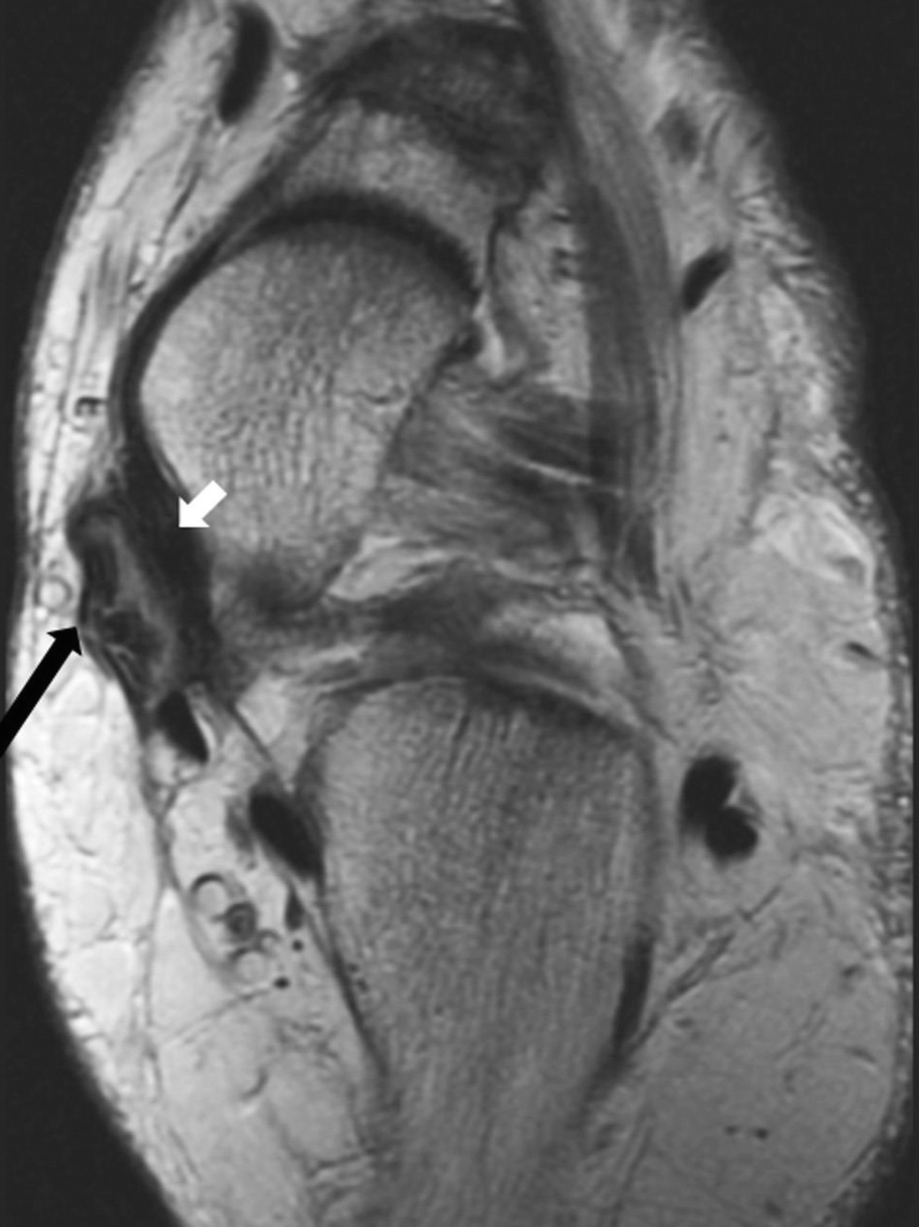

The Adult Acquired Flatfoot Springerlink